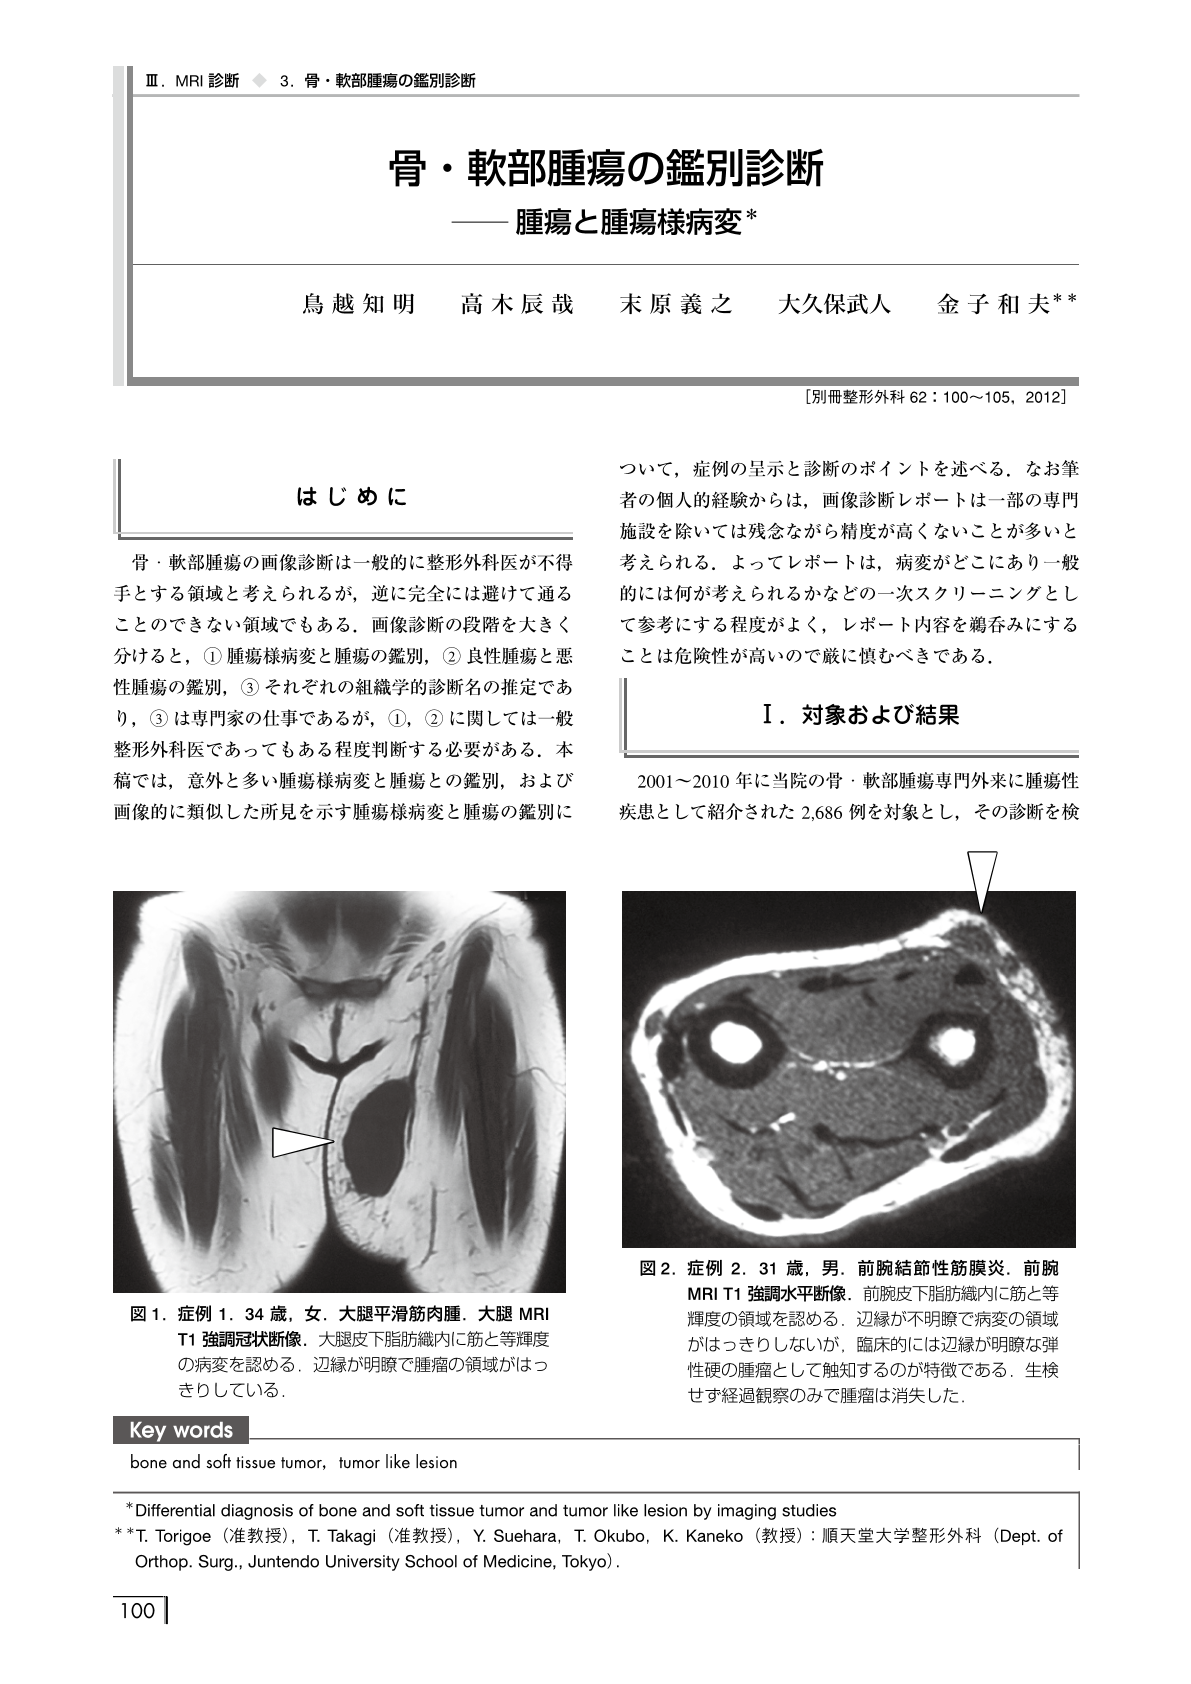

軟部腫瘍のMRI | 青木 隆敏, 青木 隆敏 |本 | 通販 | Amazon